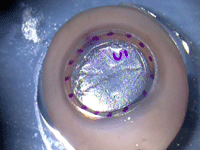

Figura 1. Presentación de una córnea donante precortada (PCT). A menudo es visible la marca de recolocación de la lamela anterior. Se puede medir el diámetro del corte.